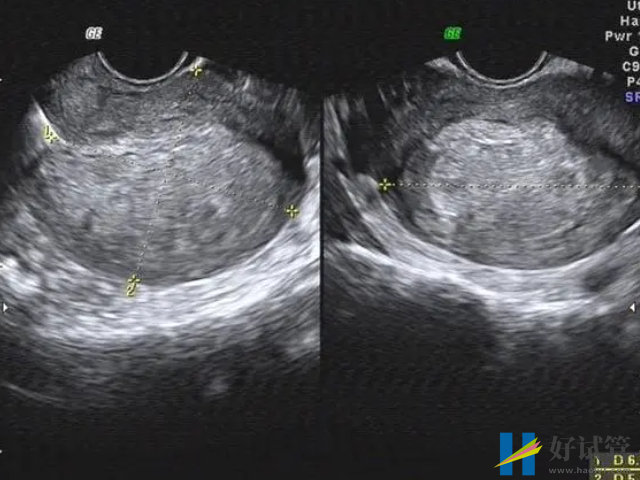

- 3. 超声检查:超声检查有助于诊断子宫息肉,但是虽然可以检测子宫内膜息肉的大小、数量和位置,但该检查不能提供明确的诊断;